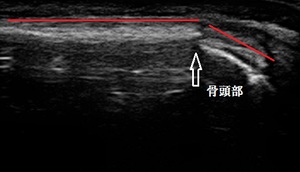

右第5中手骨 超音波長軸像 同部 整復後

超音波検査をしたところ、右第五中手骨の骨頭部が掌側に落ち込んで転位している様子が認められ

ました(左画像の矢印部が骨折部=赤線の軸が折れ曲がっている)。

骨折部を整復後、シーネ固定を行いました(右上画像が整復後=骨の軸が真直ぐに戻った)。